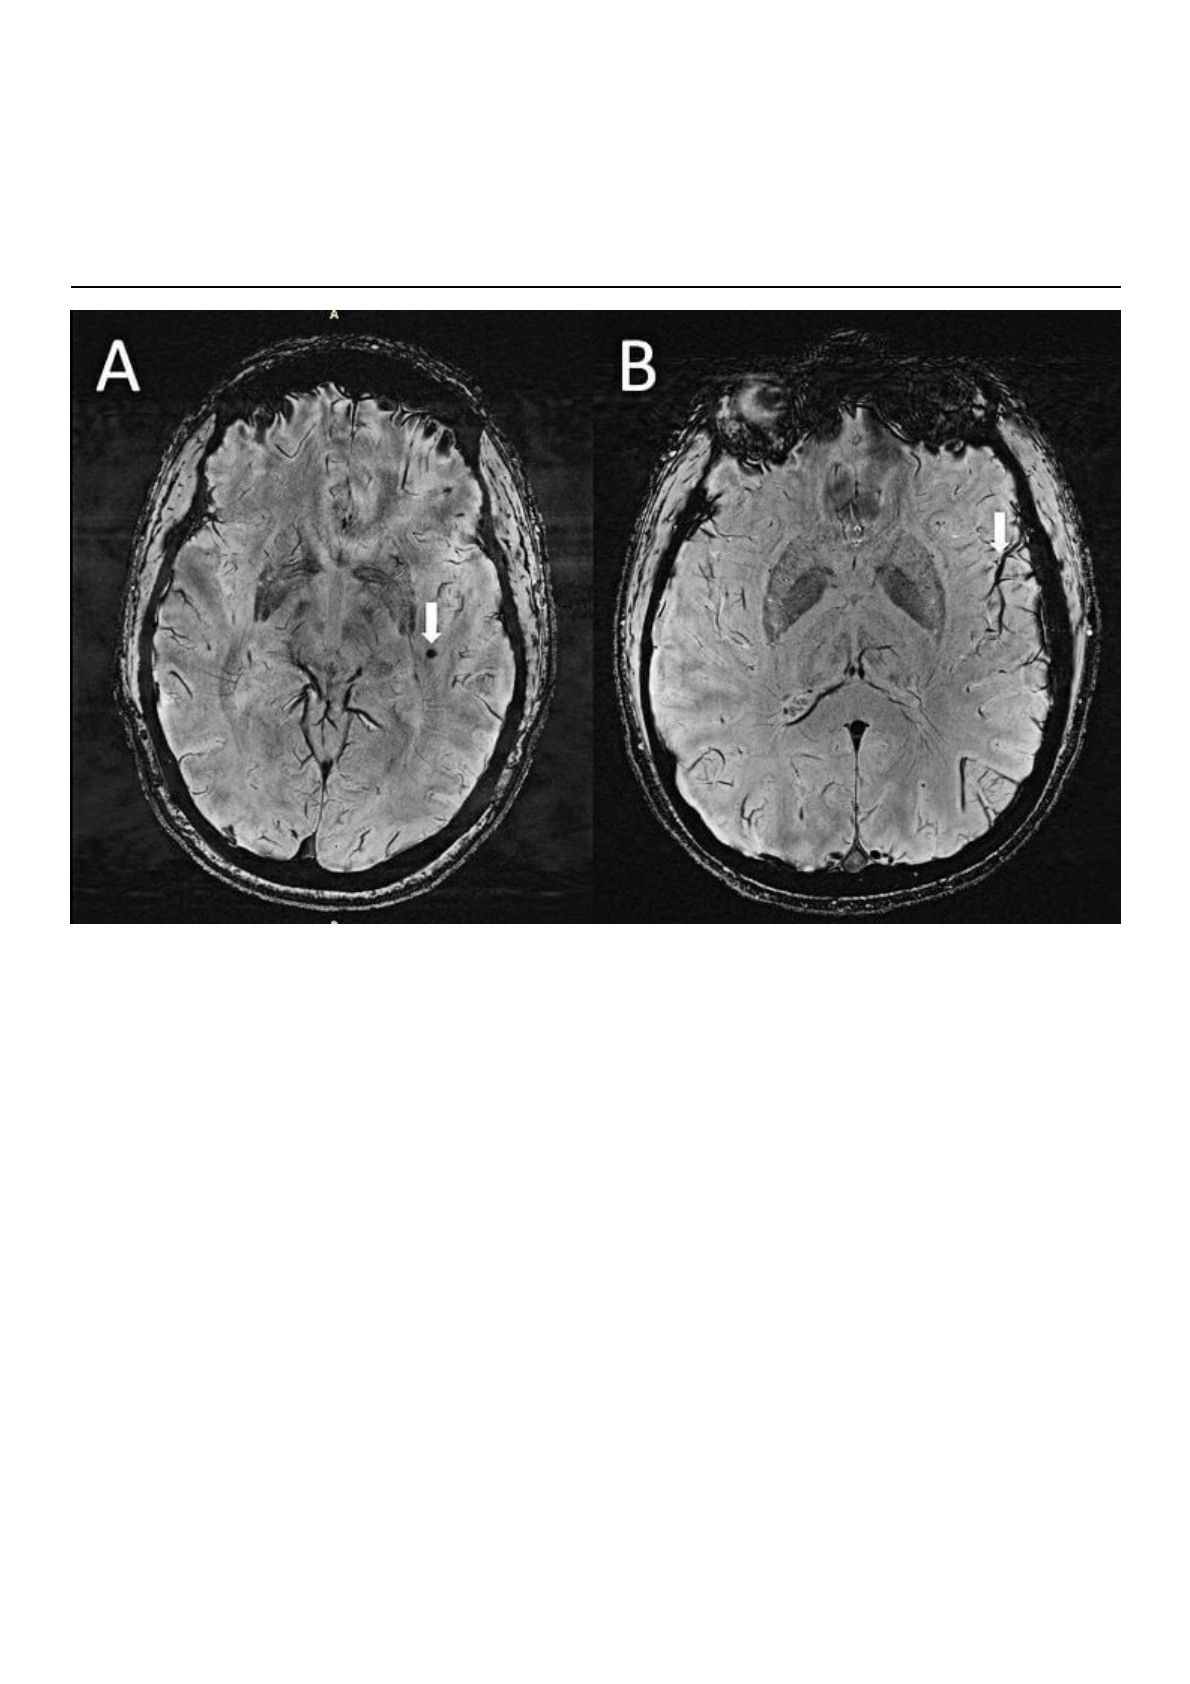

(A) Microssangramento cerebral (CMB) visualizado como lesões redondas e escuras (seta) na

sequência SWI no lobo temporal esquerdo em um caso de enxaqueca com aura. (B) A assimetria no

aparecimento dos vasos corticais é mais proeminente no lado esquerdo (seta) ipsilateral à CMB.